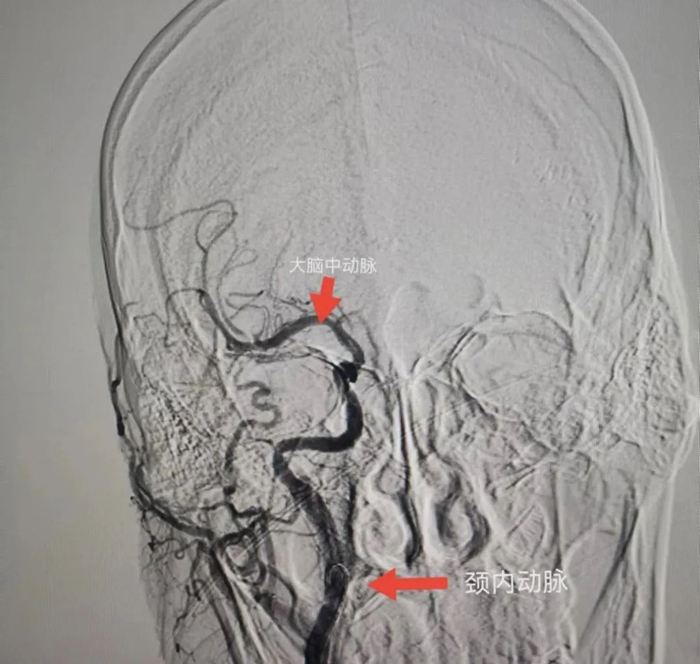

與患者女兒溝通,征得患者女兒同意后,立刻聯(lián)系CT室,半小時(shí)內(nèi)完成CT檢查,證實(shí)患者右側(cè)頸內(nèi)動(dòng)脈和右側(cè)大腦中動(dòng)脈閉塞,存在70毫升的缺血腦組織,有取栓適應(yīng)癥。再次和患者女兒溝通,患者女兒接受風(fēng)險(xiǎn)簽字手術(shù)。立刻聯(lián)系介入室和麻醉科,一個(gè)半小時(shí)完成手術(shù)。

術(shù)中給予患者右側(cè)頸內(nèi)動(dòng)脈植入支架和右側(cè)大腦中動(dòng)脈取栓,患者血管達(dá)到3級(jí)再通。術(shù)后第二天,患者神志轉(zhuǎn)清醒,左下肢可抬起。術(shù)后第5天,患者左側(cè)肢體均可活動(dòng)達(dá)到4級(jí)肌力,左手可持物,能獨(dú)立行走。

患者腦CTA結(jié)果

血管內(nèi)治療后的結(jié)果